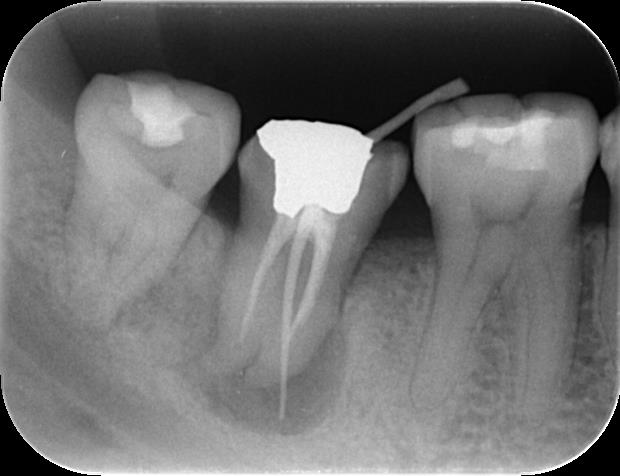

4.根管充填と支台歯築造

根管内が完全にクリーンになったことを確認したら、再感染を防ぐために薬剤で隙間なく密閉(根管充填)します。さらに当院では、感染リスクを最小限に抑えるため、根管充填を行ったその日のうちに、歯の土台となる支台歯(しだいし)を築造するところまで一貫して行います。これにより、治療した根管に細菌が再び入り込む隙を与えません。

治療後の経過をレントゲン写真で追跡したところ、治療開始から3ヶ月後には、根の先にあった黒い影(骨が溶けていた部分)が大幅に縮小し、骨が再生してきている様子が確認できました。そして、半年後には病変は消失し、健康な骨組織に置き換わっていました。